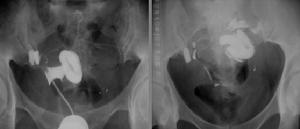

輸卵管先天性畸形不易被發現,原因首先是常與生殖道先天畸形同時存在而被忽略,其二是深藏在盆腔側方。常用的診斷方法,子宮輸卵管造影術後發現單角子宮單側輸卵管或雙輸卵管。腹腔檢查可能發現各種畸形。剖腹術可較明確的診斷。